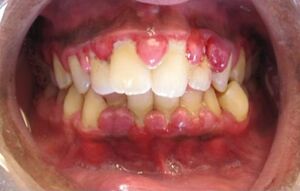

حالة التهاب لثة حادة. | |

1ـ النزف اللثوي: الذي يحدث من ضمن التلم ثم من بين الأسنان فالمناطق الضعيفة بالتدريج بسبب رقة البشرة في هذه المناطق، ويكون موضَّعاً أو معمماً بحسب شدة الالتهاب، وهو نوعان: نزف مثار لدى استخدام فرشاة الأسنان أو الأطعمة القاسية، ونزف عفوي، ولو من غير حركة، يثير القلق إذ يظن أنه دلالة على مرض دموي خبيث، ولكن هذا النزف العفوي يجب أن يكون غزيراً جداً وقلما يرقأ ليظن أنه ناجم عن سرطان الدم.

3ـ ضخامة اللثة: هي فرط نمو اللثة الناجم عن زيادة عدد العناصر الخلوية hyperplasie وعن كبر حجم الخلايا hypertrophie، مما يغيّر من شكل اللثة ويعوق استعمال فرشاة الأسنان فيتوضع الالتهاب ويزداد إمكان حدوث النزف، وتكون الضخامة موضعة أو معممة، حادة كالخراجات أو مُزْمِنة في معظم أشكالها، وتصنف بحسب السبب كما يلي:

ب ـ الضخامة الالتهابية: وهي التي تسببها اللويحة الجرثومية.

د ـ الضخامة المشروطة: وهي التي تشاهد في سياق الحمل وتسمى الورم الحملي، أو في مرحلة البلوغ أو في سياق ابيضاض الدم ونقص الفيتامين C، وكلمة مشروطة هنا تعني أن الضخامة غير قادرة على الظهور ما لم يوجد أحد هذه العوامل.